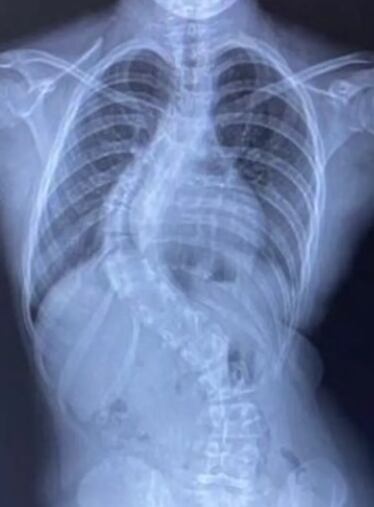

Con esos antecedentes, el dolor y la curvatura, acudieron juntas a un consultor ortopédico del Servicio Nacional de Salud (NHS las siglas en inglés) donde se le detectó una curva de 80 grados en la columna.

El médico que la revisó la diagnosticó con una escoliosis de progresión rápida y que había que intervenir de manera inmediata. “Nos dijo que había crecido siete centímetros en el último año, que es muy común sobre todo en la pubertad y que aparece casi de la noche a la mañana”, relató Burgess.

“También dijo que es muy grave y podría ser muy problemático, más que nada teniendo en cuenta la edad y cómo está creciendo. La única opción es la cirugía porque si la curva empieza a ir más lejos puede aplastar sus pulmones y el corazón “, añadió la madre.